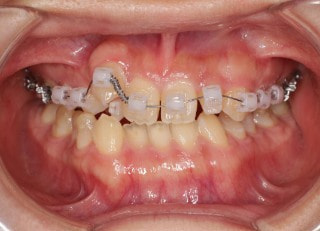

治療法:フルパッシブブラケット:T21

治療開始時

治療開始から25ヶ月後